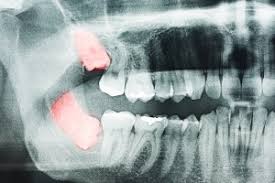

하악골(아래턱뼈) 속에는 입술과 잇몸의 감각을 느끼게 하는 신경이 지난다고 한다.

상악골(위턱뼈) 속에는 축농증이 일어날 수 있는 부분인 상악동이 있다고 한다.

이들이 사랑니 뿌리와 근접하거나 겹쳐 있는 경우가 종종 있다고 한다.

이때는 콘빔형전산화단층촬영(CBCT)을 포함한 사전 검사와 평가 후 수술을 받는 것이 좋다고 한다.